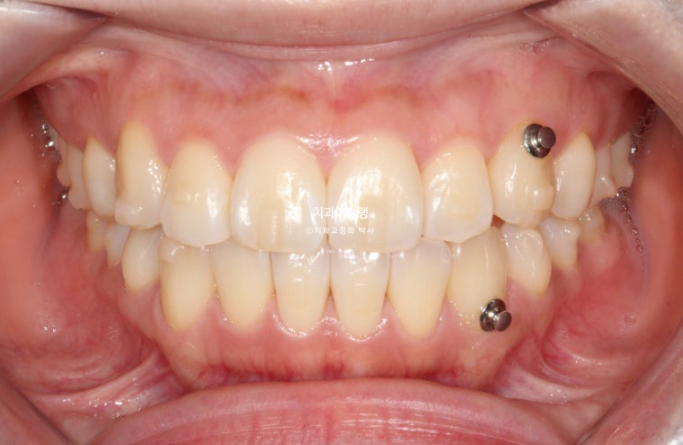

25년 3월부터 8월까지 첫세트 14개 장치를 모두 낀 후 모습입니다.

25.08

덧니 개선을 위한 고무줄 처방이 함께 들어갔으며, 메탈 고리는 고무줄 거는 고리를 치아에 붙여놓은 것 입니다.

반대교합은 해소가 되었지만 아직 중철치 - 측절기간 단차가 보이는 상태입니다.